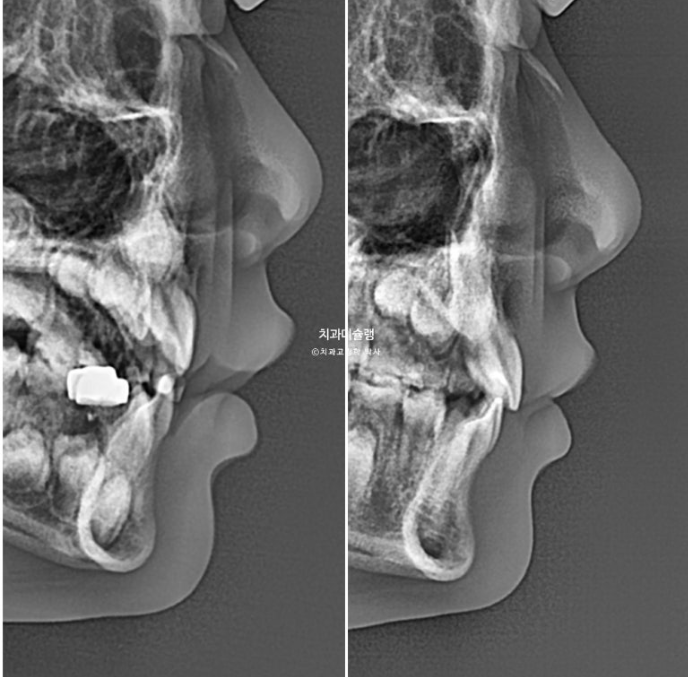

이런 부분들을 최대한 예방하기 위해서 주걱턱 (3급 부정교합)이나 무턱(2급 부정교합)이 있는 경우 시기를 미루거나 최대성장기에 맞춰서 접근해야 하고 인비절라인 퍼스트이 보증기한인 18개월을 넘어서 거의 2년까지 치료기간을 길게 잡고 있습니다,

23년 10월, 교정치료를 위해 온 어린이 입니다.

앞니 두 개 높낮이 차이, 앞니가 깊게 물리는 과개교합이 보입니다.

과개교합은 개선되었고 측절치 나올 공간을 악궁확장으로 미리 벌려줬기 때문에 측절치는 잘 내려왔습니다.

중심선은 잘 맞아졌고 과개교합은 더 개선이 되었습니다.

두번째 추가장치 16개를 모두 낀 후 치료를 종료했습니다.

유지장치는 과개교합 재발을 방지하기 위해 교합판이 들어간 유지장치를 잘때만 낍니다.

이제 전 후 비교 보겠습니다.

23.10~25.08